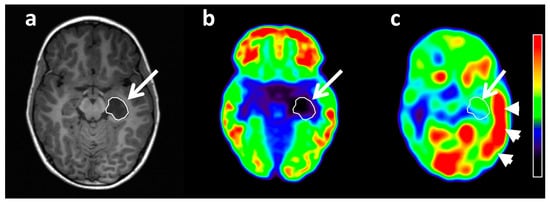

- Unterrainer, M.; Fleischmann, D.F.; Diekmann, C.; Vomacka, L.; Lindner, S.; Vettermann, F.; Brendel, M.; Wenter, V.; Ertl-Wagner, B.; Herms, J.; et al. Comparison of 18F-GE-180 and dynamic 18F-FET PET in high grade glioma: A double-tracer pilot study. Eur. J. Nucl. Med. Mol. Imaging 2019, 46, 580–590. [Google Scholar] [CrossRef]